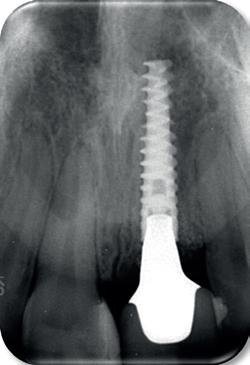

De implantaatplaatsing en de beslissende fout (afbeelding 1-13)

De extractie verliep voorspoedig, waarbij ik zoals al-

primaire stabiliteit van 60 Ncm.

11. Röntgenfoto ter controle van de plaatsing en de angulaire. Dit bone-level implantaat werd 4 mm onder de weke delen geplaatst.

tijd probeerde de buccale botlamel intact te houden. Dit is cruciaal voor latere botbehoud en implantaatplaatsing. Na curettage en spoelen van de alveole beoordeelde ik de situatie opnieuw: de botcondities leken gunstig voor een immediaat implantaat.

Hier begon echter de cruciale fout in mijn klinisch besluitvormingsproces. In mijn streven naar maximale primaire stabiliteit - wetende dat immediaat belasten enkel mogelijk is bij hoge stabiliteit -on-

derprepareerde ik de osteotomie. Dit betekende dat ik een iets te smal implantaatbed creëerde, in de hoop dat het implantaat stevig in het bot verankerd zou worden.

Op papier leek dit een logische stap: het MegaGen AnyRidge-implantaat dat ik koos, gaf me een stabiliteit van 60Ncm—een cijfer dat vertrouwen gaf in immediaat belasten. Maar in mijn enthousiasme had ik onvoldoende rekening gehouden met de biologische gevolgen van overmatige compressie.

Door de te hoge druk op het omringende bot verminderde daarin de doorbloeding, wat leidde tot een verhoogd risico op botnecrose. Dit was geen fout van abutmentkeuze of occlusie; dit was puur het gevolg van mijn drang naar optimale stabiliteit en de wens om het implantaat direct te belasten, onder invloed van patiëntdruk.